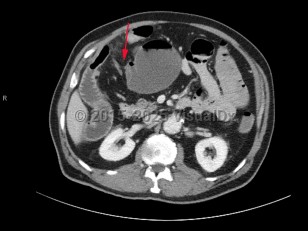

A small bowel obstruction (SBO) occurs when intraluminal bowel contents fail to pass through the small intestine. Impaired passage of bowel contents results in dilation of the proximal bowel, with fluid accumulation, gas production, increased intraluminal pressure, and bacterial overgrowth. This results in abdominal distension and pain, nausea, and vomiting, with risk of bowel ischemia and perforation.

SBOs can be classified as partial or complete. Partial SBOs permit some passage of bowel contents past the obstruction site, while complete SBOs are associated with the inability to pass any gas or fluid past the obstruction. Partial SBOs can further be stratified into high-grade or low-grade, depending on the severity of obstruction, with low-grade SBOs presenting with less severe symptoms. A simple SBO is characterized by a single point of obstruction. A closed-loop obstruction is characterized by occlusion of the bowel at 2 points and has the highest risk of ischemia due to occlusion of the blood supply.